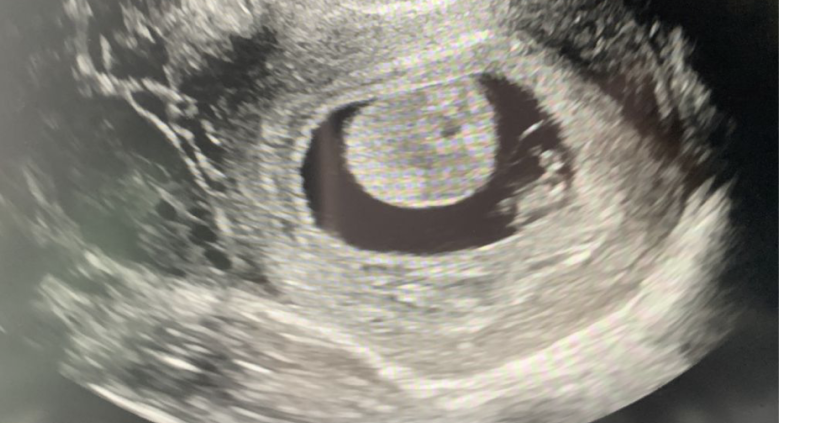

Какво представляват белите точки в плодния сак на ехографската снимка?

Какво представлява жълтото тяло на ехографската снимка?

Дали някой е минал през това и така ли изглежда в тези ранни седмици? Тя беше доста объркана, затова се допитвам тук…